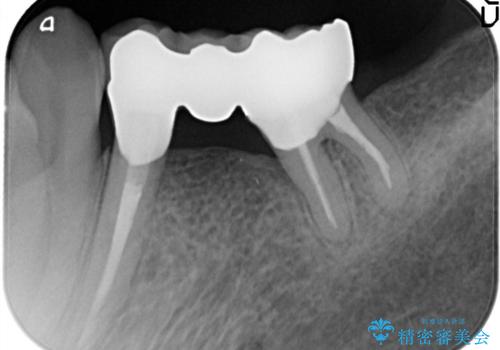

金属のかぶせ物をセラミックへ 根管治療からの再治療

左側の上下の奥歯に適合が悪く、レントゲン上でも根の治療が必要なところがありました。

再治療を行いました。

根管治療からの再治療を行ったことにより、治療期間が多少長くなりましたが、今後再治療の必要性があまりないような、精度の高い治療ができました。